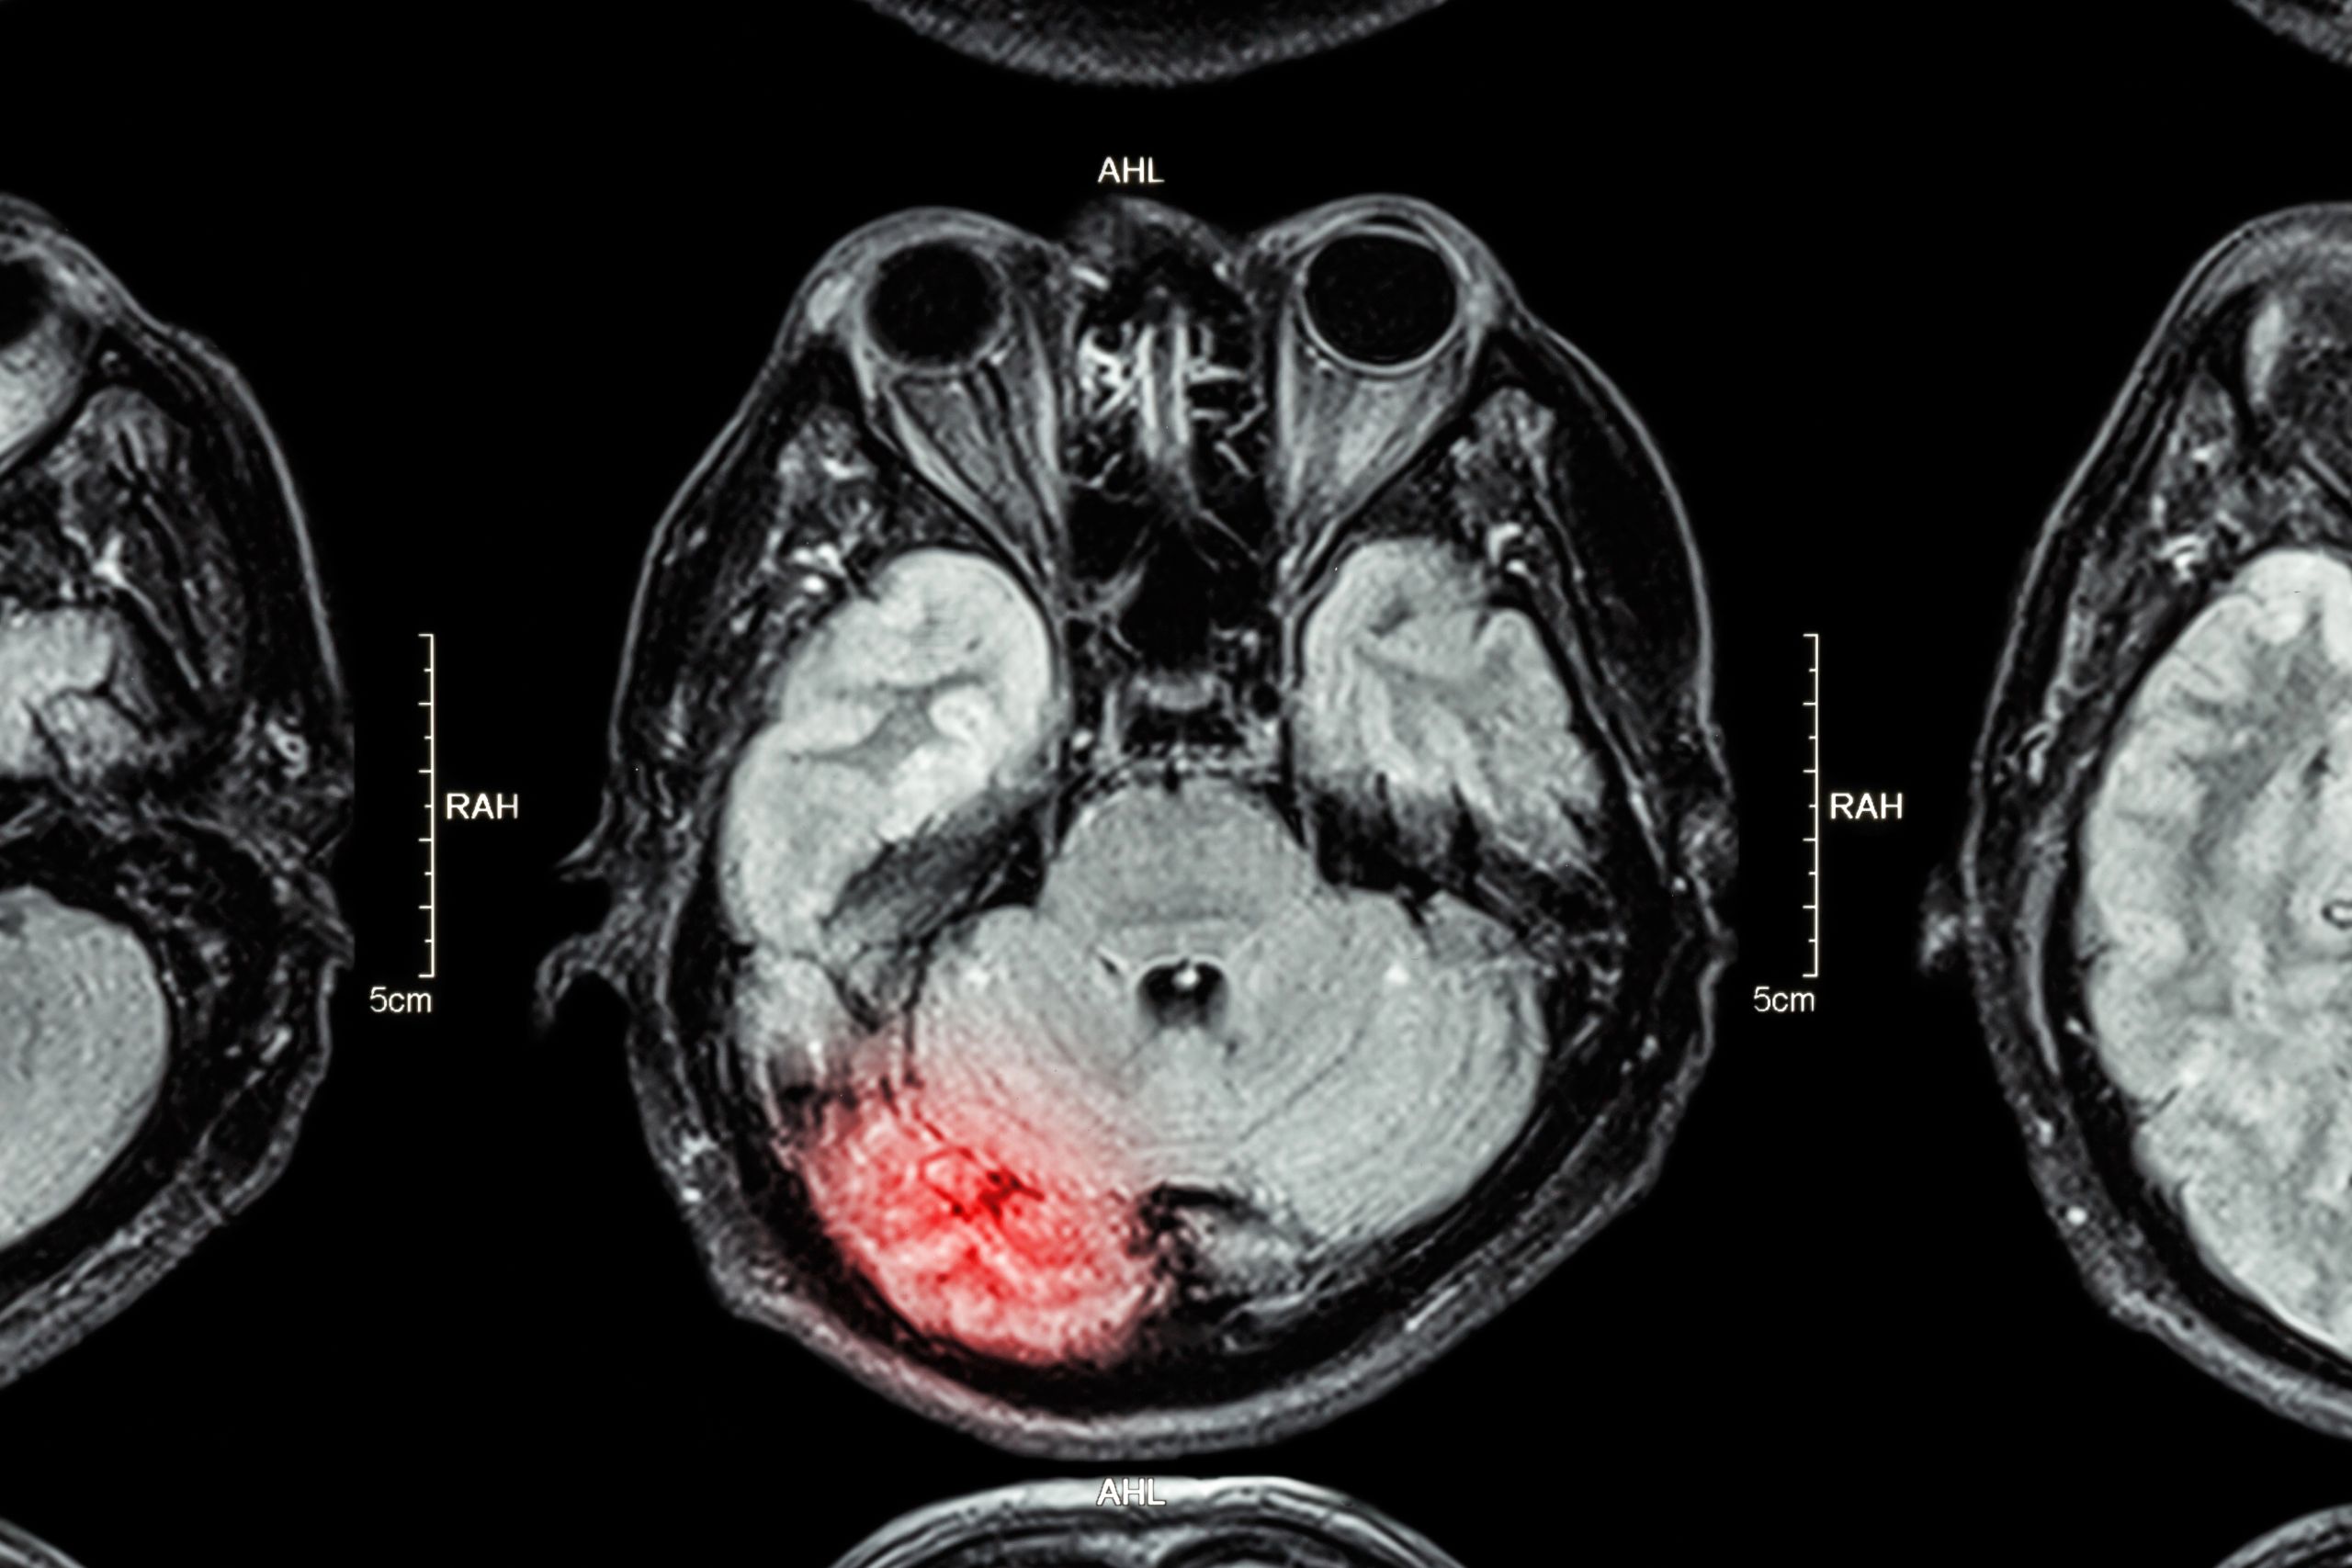

Traumatic brain injury (TBI) is among the most significant injuries former combat veterans suffer. According to health officials, there has been an uptick in TBI in military service members who served in Afghanistan and Iraq.

Traumatic brain injuries are disruptions of brain function arising from a jolt or blow to the head or penetrating head injury. A closed head injury does not expose the brain to damage. A penetrating or open head injury happens when an object pierces the skull and damages the outermost membrane covering the brain.